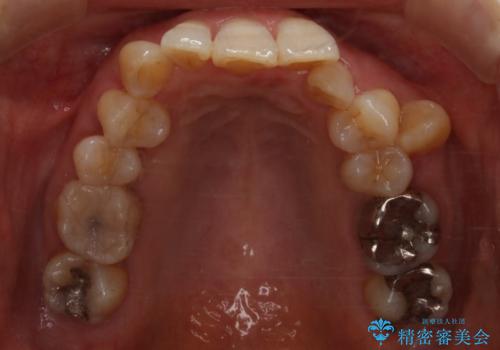

- 上下の歯のがたつきと、噛み合わせが深いことを気にされてご相談にいらした方です。噛み合わせに参加していない歯を抜歯してインビザラインにて治療を行いました。

一般的に噛み合わせの深い方へのインビザライン治療は適応が難しいとされていますが、今回は噛む力を上手にコントロールできたことと、内側に入り込んでいた前歯の角度を調整したことで下の歯がしっかり見えるようになりました。短期間で劇的に見た目が改善し、大変喜んでいただけました。